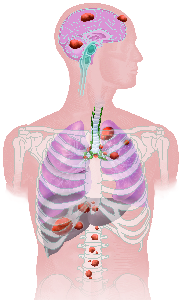

Detailreiche Fotografien aus der medizinischen Praxis ergänzen die Texte; moderne, genaue,

wissenschaftliche Zeichnungen geben Einblick in die Anatomie und die Funktion der Lunge und

anderer Organe.